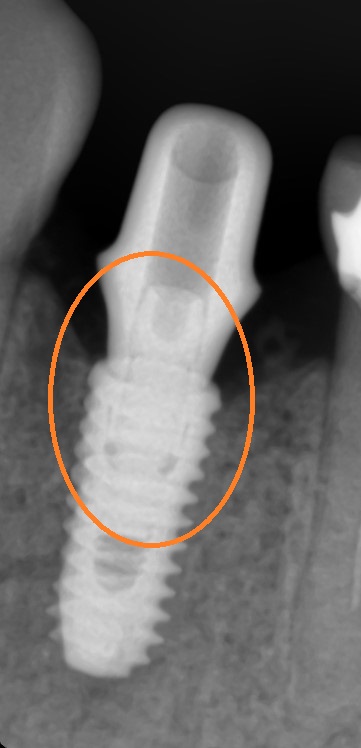

주황색 동그라미의 작은 나사를 조여줄 수 있는 상태로 판단이 되고

잘 조여주게 되면

1과 2가 분리되어 흔들리던 것이

고정이 되는 것입니다.

보통은 1의 픽스쳐가 뼈랑 단단히 유착되어 있어 픽스쳐가 흔들리는 경우보다는

1과2사이 나사가 풀려 머리부분이 흔들리는 경우가 더 많은데요

그런데 이번에 소개해 드릴 케이스는 1,2사이의 작은 나사를 쪼여서 해결될 문제가 아니라

다른 치과에서 오래 전에 한 임플란트가 1이라고 표시해드린 뼈에 박힌 픽스쳐가 많이 흔들리는 상태였습니다.